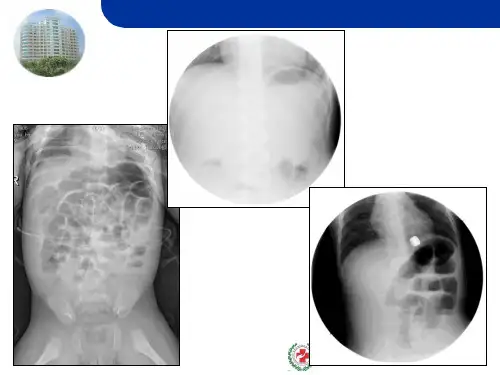

肠套叠影像学(最新课件)